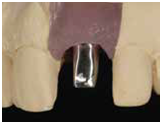

由於前後植體的高低差距太大,決定將中間兩顆高度較為一致的植體假牙做連結,但前後兩顆做單顆假牙的設計。

100/11/21 補綴完成